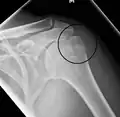

Multi-fragmented, or comminuted fracture of the proximal humerus with involvement of the greater tuberosity

Proximal humerus fracture